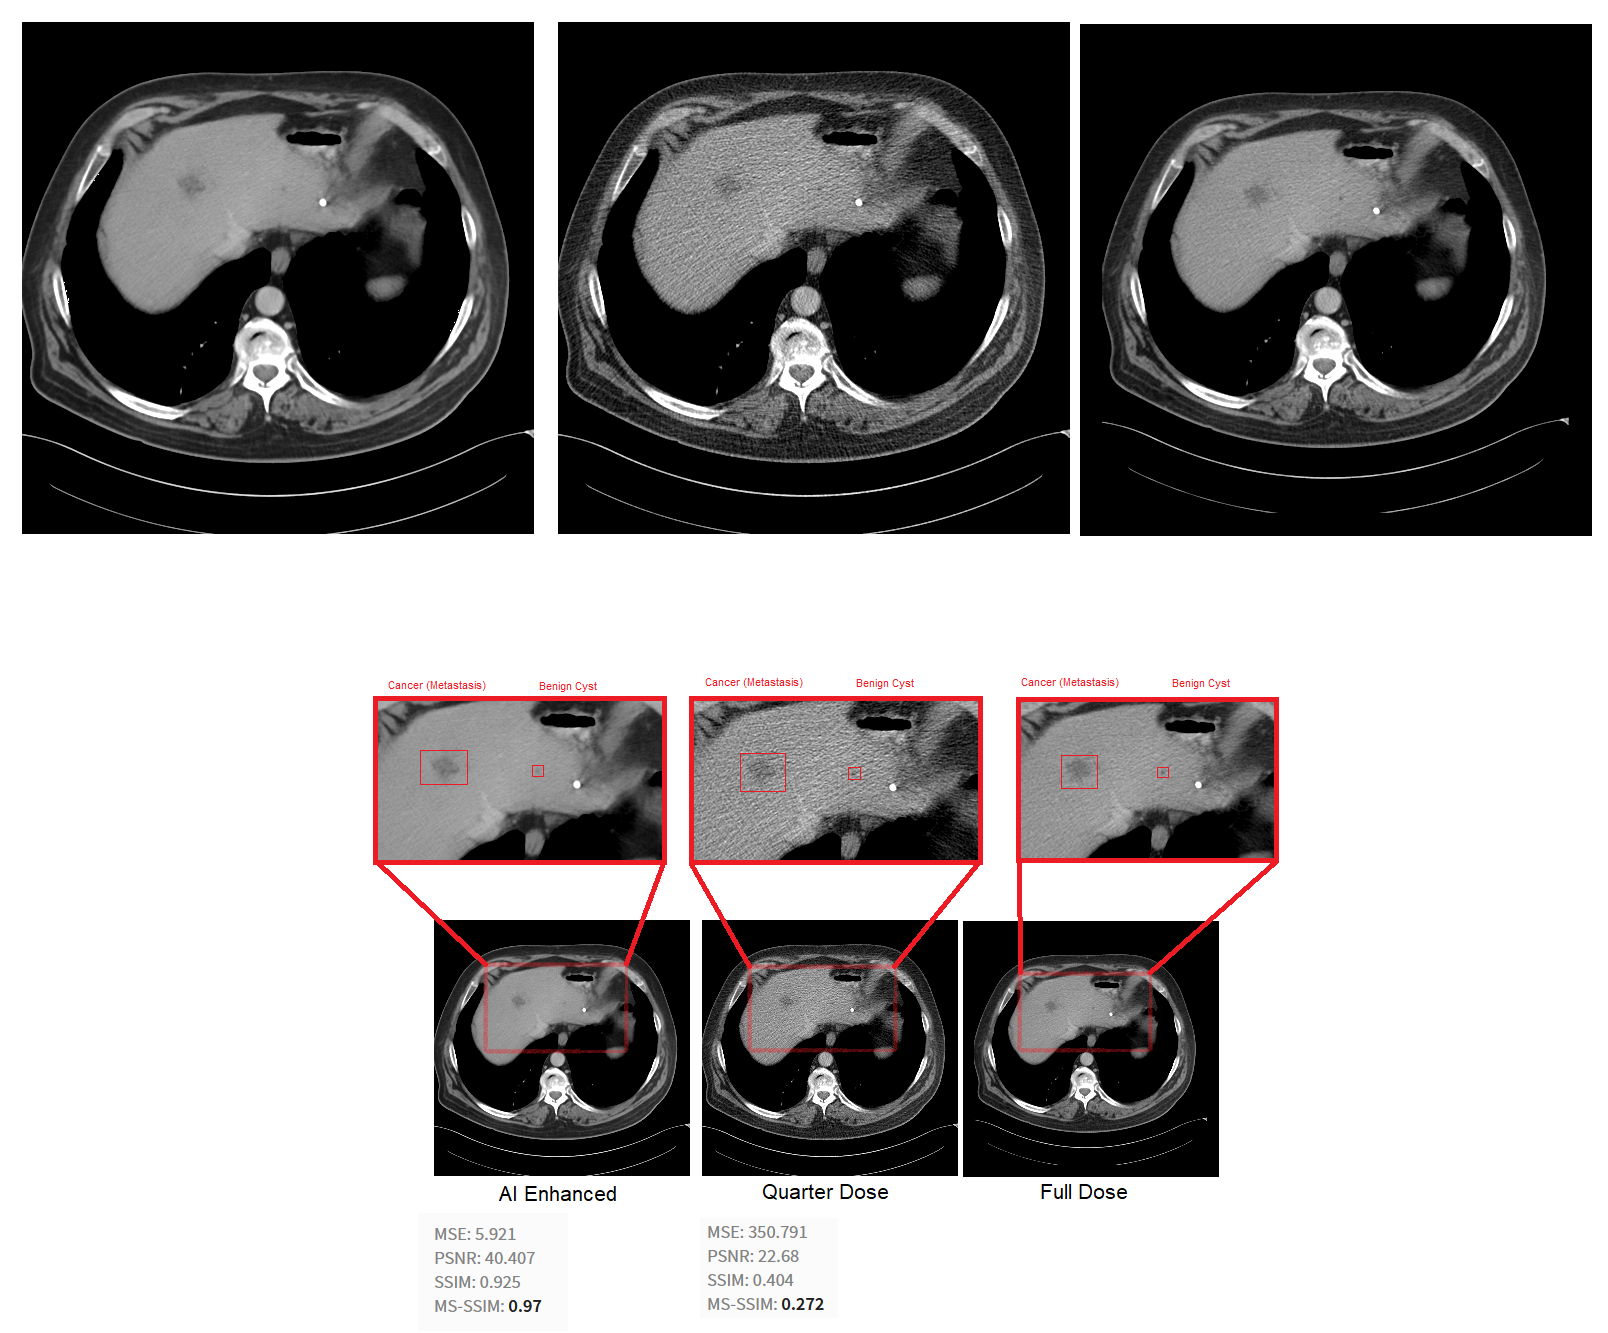

Clearer Images, Better Diagnostics

The AI-enhanced scans were significantly sharper than the originals. Key diagnostic features—like tumors in liver scans—became easier to detect after denoising.

- PSNR (Peak Signal-to-Noise Ratio): Improved from ~22.68 to 40.41

- SSIM (Structural Similarity Index): Reached 92.5%, indicating strong structural preservation

These metrics confirm the model’s ability to reduce noise while maintaining important image details.